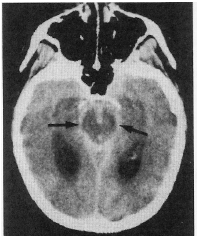

Com relação à imagem mostrada na figura abaixo, julgue o item que se segue.

A incidência de aneurismas na circulação posterior é de apenas 4%.